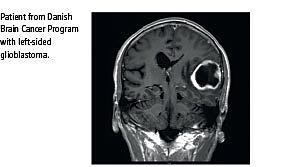

I 2009 blev pakkeforløb for »kræft i hjernen« etableret. Indgangskriterierne til hjernekræftpakken er inddelt i fem grupper: 1. Computertomografi eller magnetisk resonans (MR)-skanning har påvist intrakranial rumopfyldende proces. 2. Nyopstået fokalt neurologisk udfaldssymptom progredierende over dage/uger. 3. Nyopstået epileptisk anfald hos voksne. 4. Progredierende og nyopstået adfærds-/personlighedsændring eller kognitive deficit (APKD). 5. Nyopstået hovedpine eller ændring i hovedpinemønster, progredierende over 3-4 uger. Det blev af Sundhedsstyrelsen forventet, at man hos ca. 10% af patienterne i hjernekræftpakken ville få påvist enten malign eller benign intrakranial tumor.

Vi fandt 21 MR-verificerede tumorer; heraf var otte primære maligne intracerebrale tumorer, fem meningeomer, tre hypofysetumorer, fire metastaser hos patienter uden kendt primær cancer og en ekstracerebral tumor. Yderligere 25 patienter havde anden akut eller subakut patologi. I gruppen med monosymptomatisk hovedpine var der signifikant færre tumorer (p = 0,0066) end i den samlede gruppe. Ligeledes sås der signifikant færre akutte/subakutte diagnoser (p = 0,0008). I gruppen med APKD sås signifikant flere primære intracerebrale tumorer (p = 0,0002), flere tumorer i alt (p = 0,0001) og flere med akut/subakut patologi i forhold til den samlede gruppe (p = 0,0002), men gennemsnitsalderen i denne gruppe var dog betydeligt højere end i hele gruppen: 57,9 år (53,3-62,4) mod 47,5 (45,5-49,5).